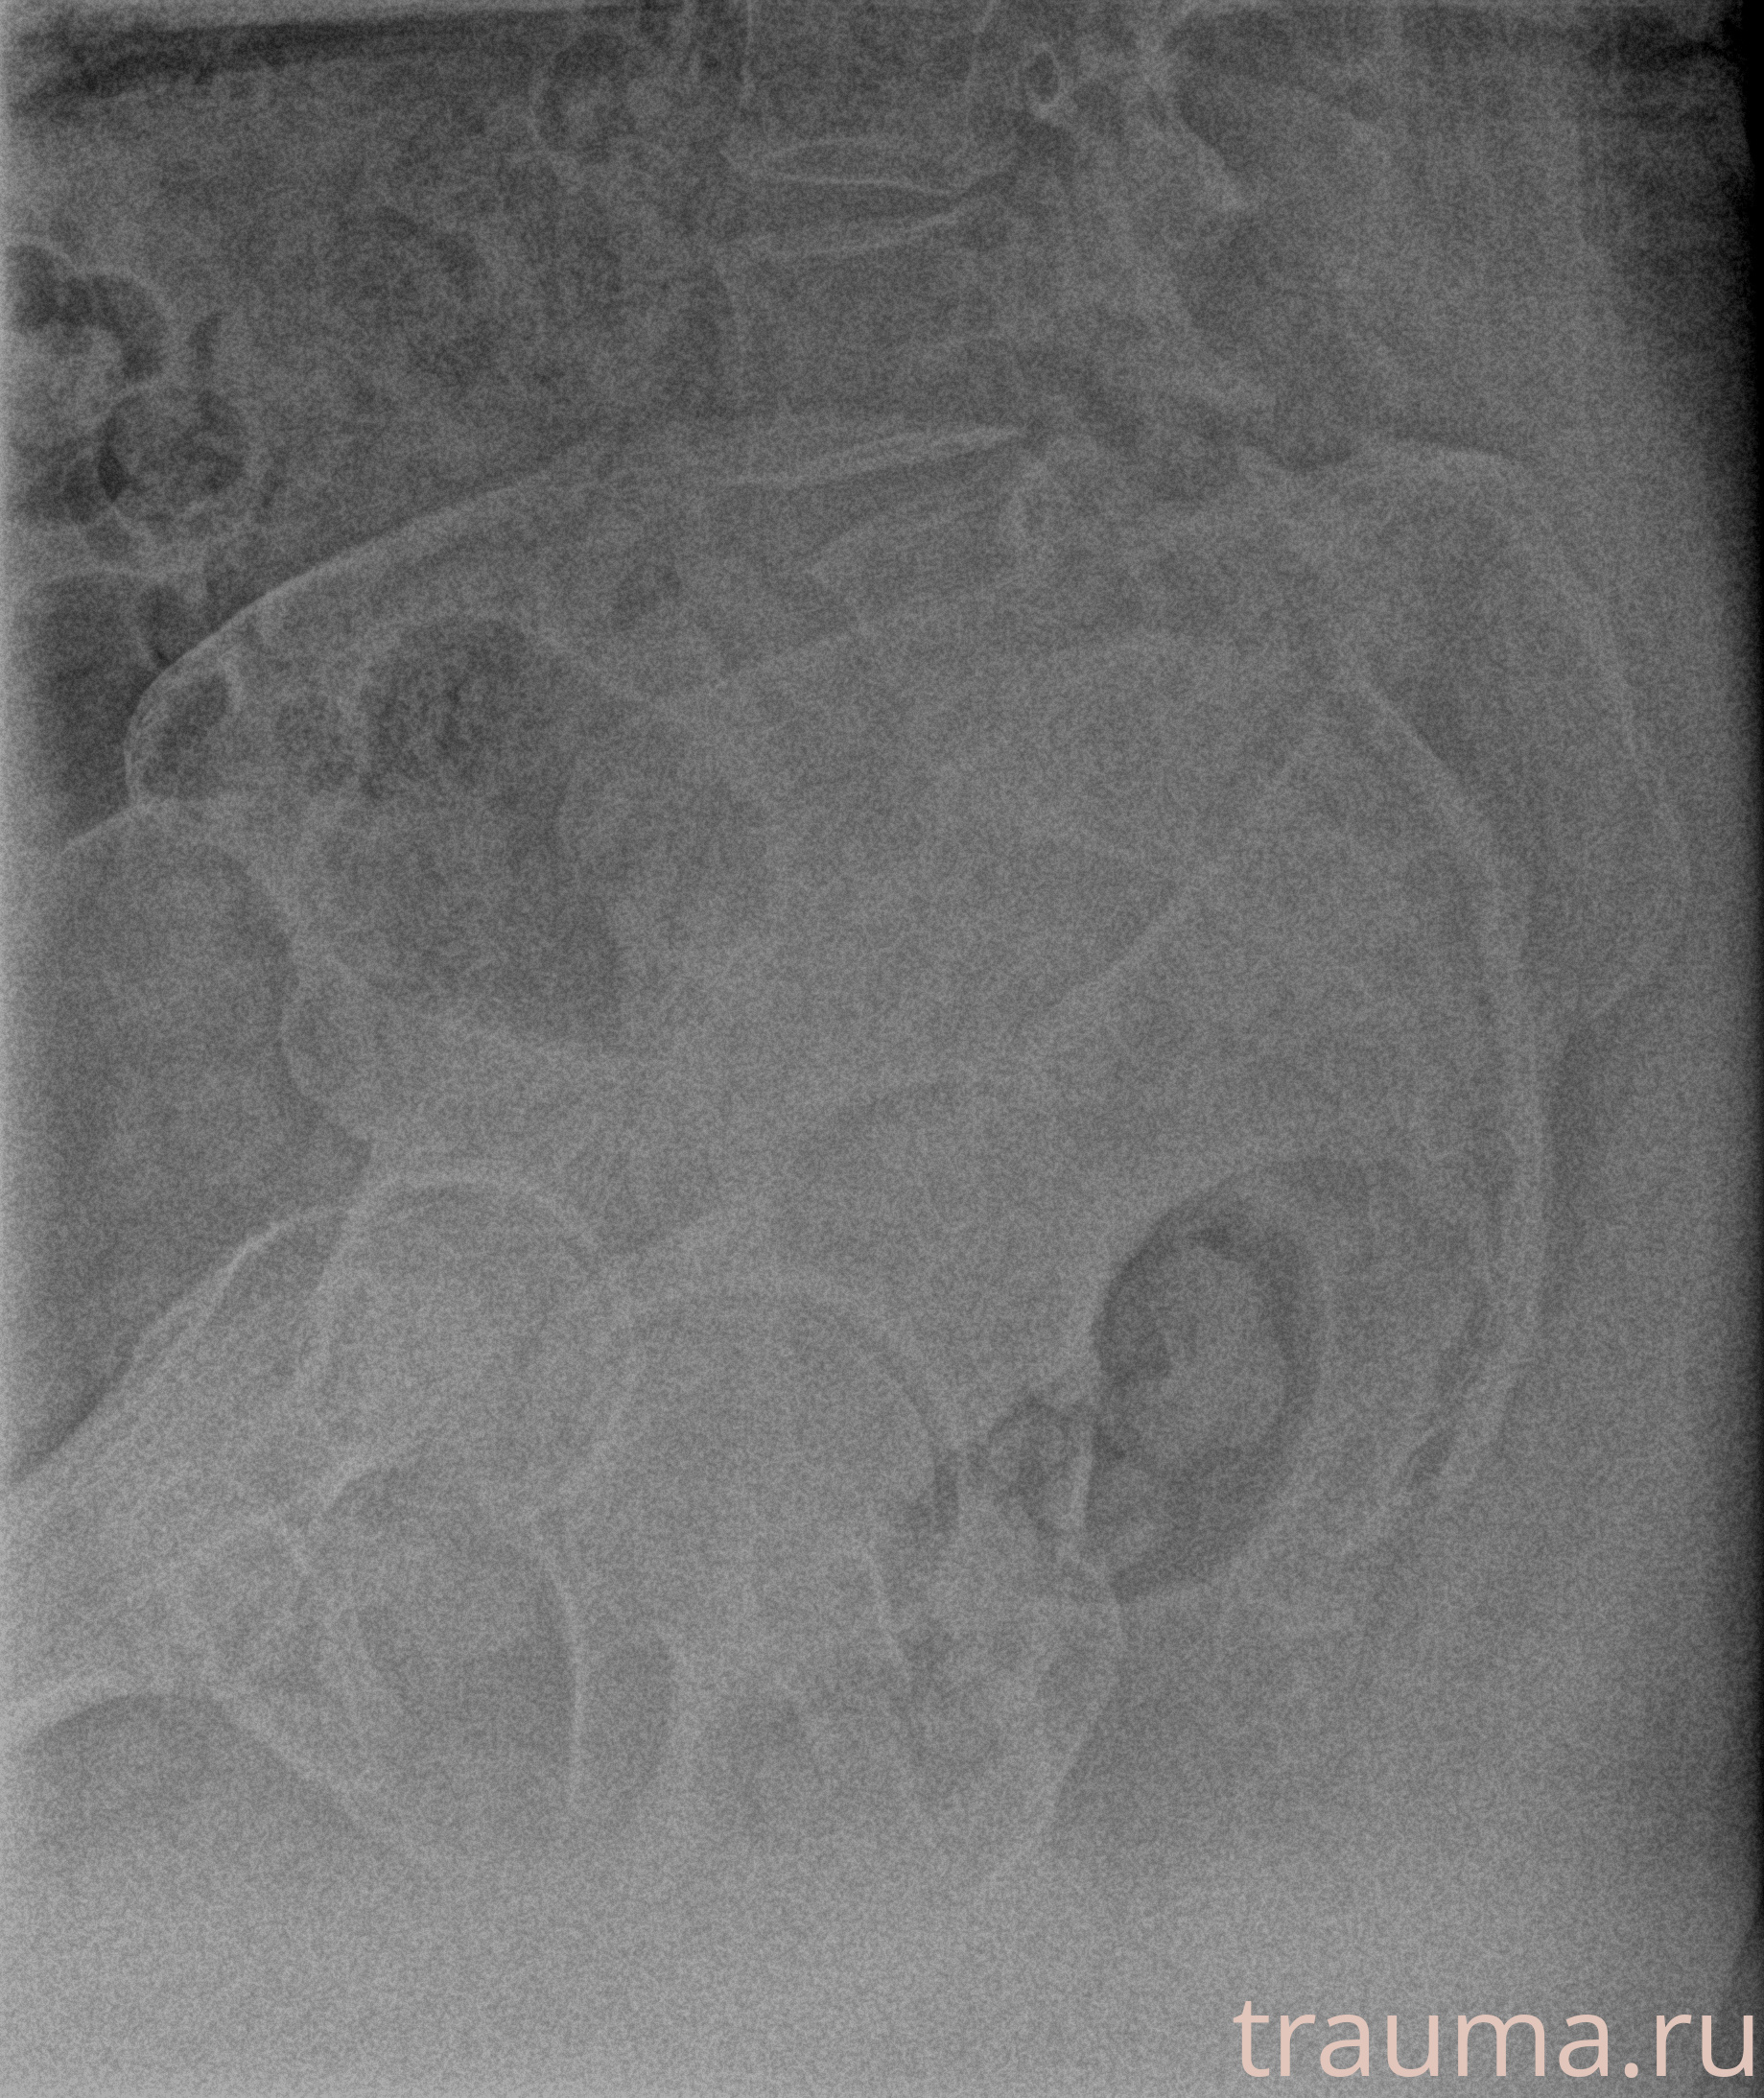

Первая помощь при переломе шейки бедра

Рентген на дому: по вашему адресу приезжает врач-рентгенолог, травматолог-ортопед с мобильным рентгеновским аппаратом, проводит диагностику травмы или заболевания, делает необходимые рентгенограммы, дает рекомендации по дальнейшему лечению. Получить качественные снимки в домашних условиях возможно благодаря уникальной методике, разработанной МосРентген Центром для института  Склифосовского